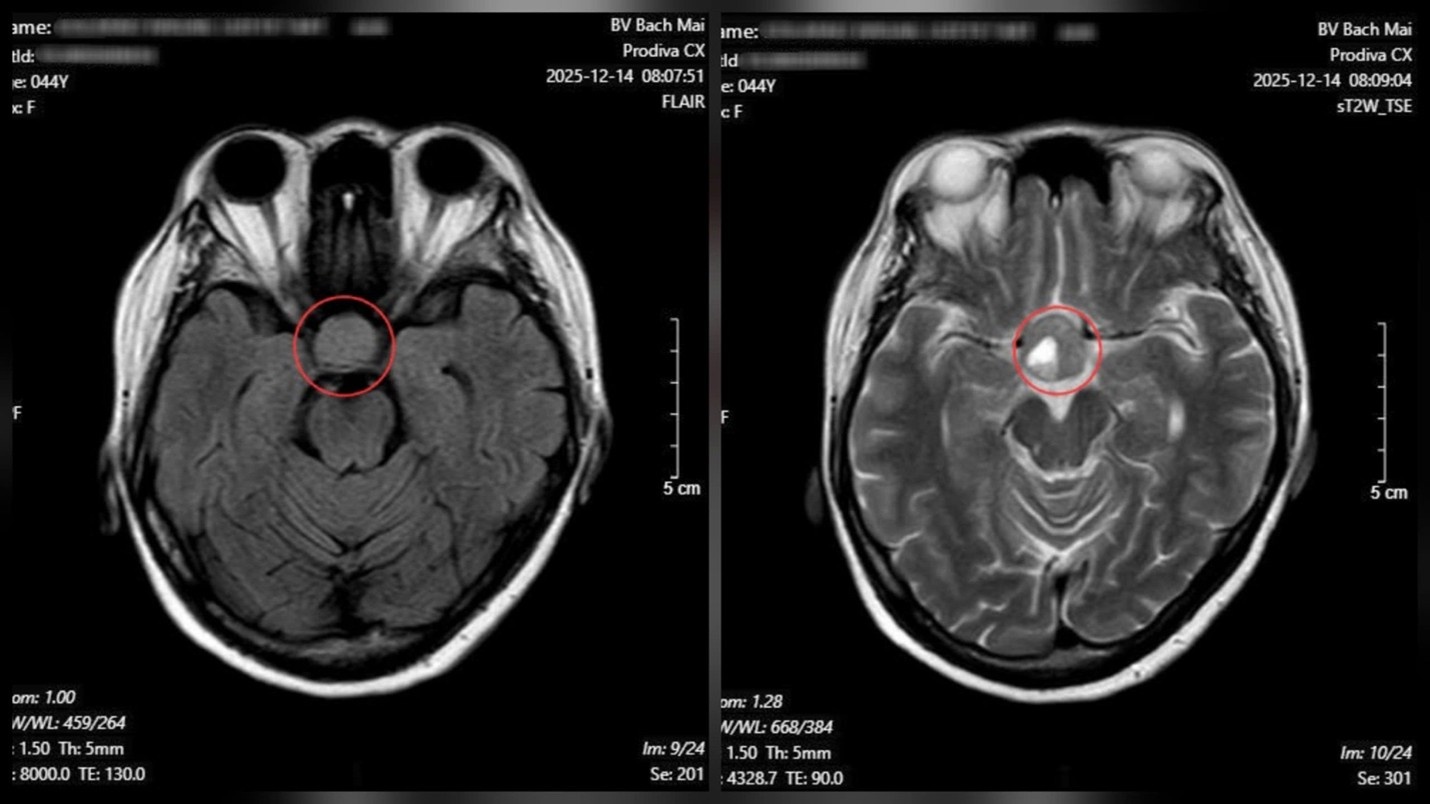

Từ những dấu hiệu nghi ngờ trên, bệnh nhân được chỉ định chụp cộng hưởng từ (MRI) sọ não. Kết quả cho thấy một khối u tuyến yên kích thước lớn (macroadenoma) với đường kính khoảng 26 × 21 mm.

Kết quả chụp cộng hưởng từ (MRI) sọ não cho thấy một khối u tuyến yên kích thước lớn. Ảnh: BVCC.